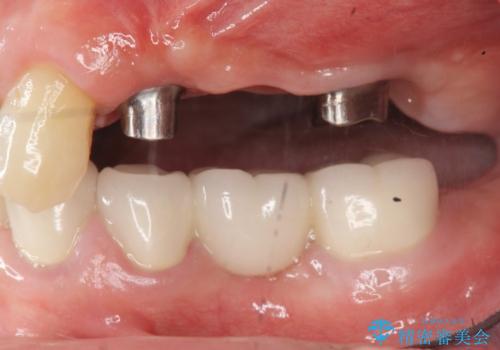

- 治療計画

- 重度の虫歯により左上の歯を失い、インプラント治療は怖いため嫌厭して放置していたが、いよいよ食事に困りしっかりと噛めるようになりたいと希望され来院されました。

残存している小臼歯も虫歯が大きく保存が難しいため抜去を行い造骨を含めたインプラント治療を行います。